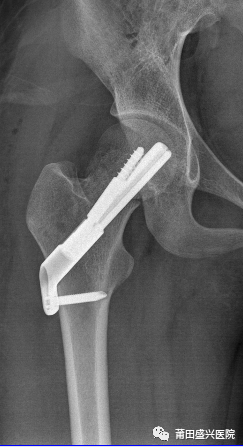

經(jīng)盛興醫(yī)院骨科團(tuán)隊(duì)綜合評(píng)估后,決定為患者實(shí)施“右股骨頸骨折微創(chuàng)復(fù)位FNS內(nèi)固定術(shù)”治療。在林國(guó)兵院長(zhǎng)、黃益平主任醫(yī)師及骨科團(tuán)隊(duì)的共同努力下,手術(shù)于2022年1月18日在麻醉科及手術(shù)室醫(yī)護(hù)的全力配合下順利完成,術(shù)后透視復(fù)位佳,內(nèi)固定位置良好?;颊咝g(shù)后1周康復(fù)出院。

(術(shù)后2天復(fù)查)